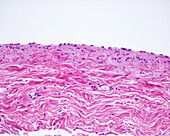

13613516 - Vein adventitia, light micrograph